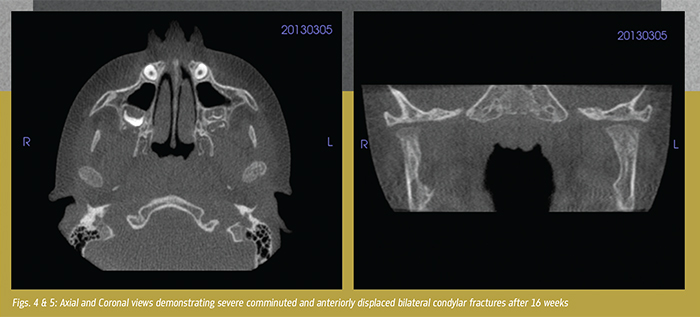

An eight-year-old boy was involved in a significant accident where he struck his jaw, sustaining multiple mandible fractures and bilateral comminuted displaced condylar fractures (Figs. 1-3). Subsequently, he was treated with an open reduction of the body fracture and three-and-a-half weeks of closed reduction of the condyles due to the multiple comminuted segments.

The patient was followed with low dose 3D imaging through a period of progressive mobilization and "guiding" elastic inter-maxillary fixation with physical therapy using Rocabado 6x6x6 protocol. The goal was to improve his range of motion, gain consolidation of the condylar fragments, and prevent ankylosis. Over the intervening months, follow up was completed to monitor consolidation of the condylar segment, the development of new articulation and growth of the condyles to a more normalized position (Figs. 4-5).